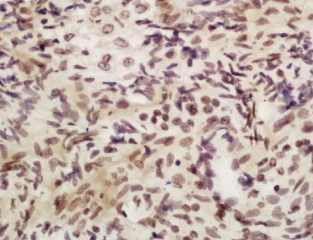

组织/细胞:大鼠卵巢组织;4%多聚甲醛固定石蜡包埋;

抗原提取:柠檬酸缓冲液(0.01M,pH 6),15min煮沸,用3%过氧化氢阻断内源性过氧化物酶30min;37℃下阻断缓冲液(正常山羊血清,C-00 05)20 min;

孵育:抗apobec3b多克隆抗体,未结合(BS-12494R)1:200,4°C下过夜,然后与二级抗体结合,DAB染色。